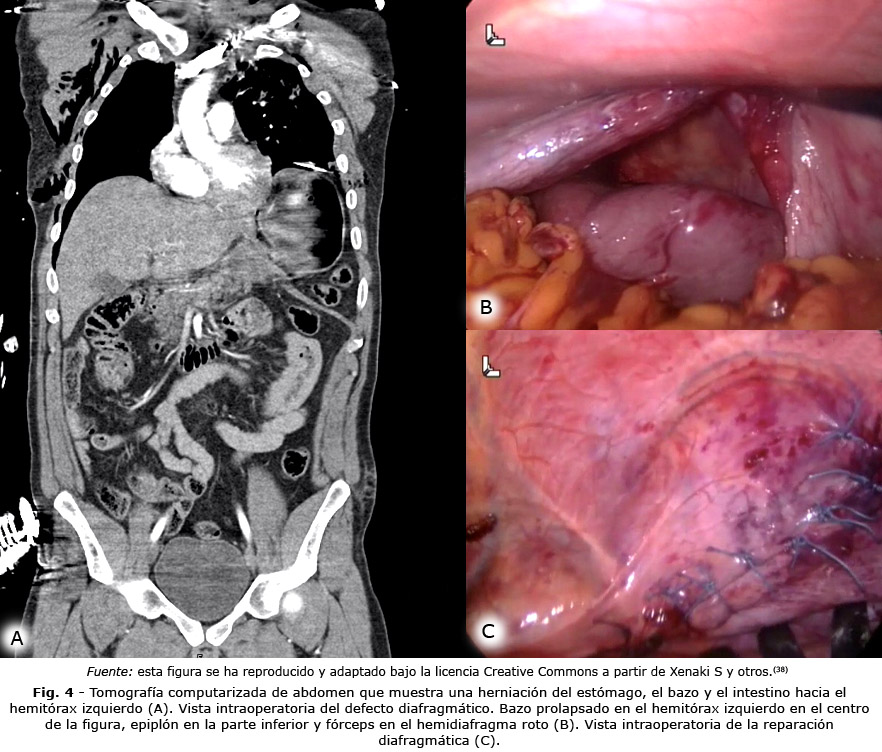

El desempeño de la TAC varía de acuerdo con el mecanismo del trauma, al ser menor de forma significativa en trauma penetrante. Existen diferentes signos tomográficos (Fig. 4) que sugieren ruptura diafragmática, dentro de los descritos con mayor frecuencia se encuentra la evidente discontinuidad o el defecto focal del diafragma, la herniación de vísceras abdominales intratorácicas, el signo del collar, el signo de la víscera dependiente o el signo de la joroba.(10)

En el escenario del trauma diafragmático, los procedimientos de video cirugía, ya sea laparoscopia o toracoscopia, se han convertido en el método de referencia (gold standard) por la posibilidad del diagnóstico y el tiempo de tratamiento simultáneo (Fig. 4). Esto ha hecho que la laparotomía, que antes era obligatoria en estos pacientes, esté indicada como primera opción en los casos en los que existe inestabilidad hemodinámica.(11,36,37)